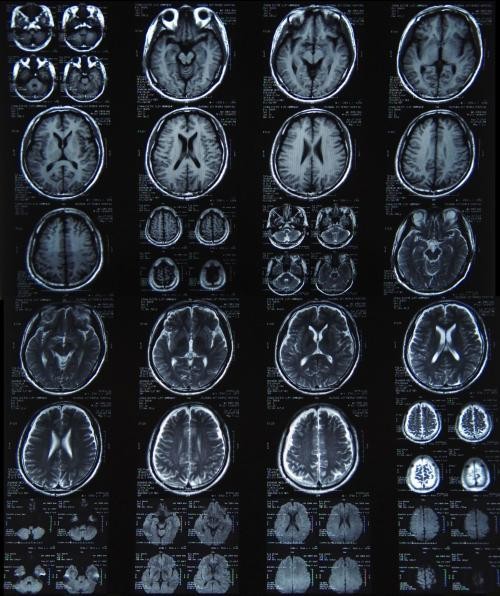

(图)脑部CT片

从X光到CT的突破和进步,我们可以广义的理解为:医生从一个长方形到从一个长方体看病变区域的突破。

(图)一张脑部核磁共振成像,它为医生提供了更多角度

“横看成岭侧成峰,远近高低各不同”,苏轼用来描写庐山的名句,其实很多时候也可以用来形容病变区域。对病变区域的观察,横看、侧看、上看、下看对结果都有着不同影响。医生要想全面、细致的了解病变区域的“全貌”,就要求检查手段能够提供不同方向的成像。

核磁共振的一个巨大技术突破,就是可以对人体进行横断面、矢状面、冠状面三维任意角度切层,这就保证了医生只要有需要,可以从任何角度观察病变区域。除此之外,没有电离辐射也是核磁共振的一大优势。

医院里一般都是这个程序,X光没拍出来的,医生会建议再拍CT。最适于CT检查的病是脑部疾病,其中对肿瘤、出血及梗塞等病检查效果最好,其次是腹部实质脏器的占位病变,如肝、脾、胰、肾、前列腺等部位的肿瘤,对乳腺、甲状腺等部位的肿块也能显示并做出诊断;再次则是对胸腔、肺、心腔内的肿块,脊柱、脊髓、盆腔、胆囊、子宫等部位的肿块检查。